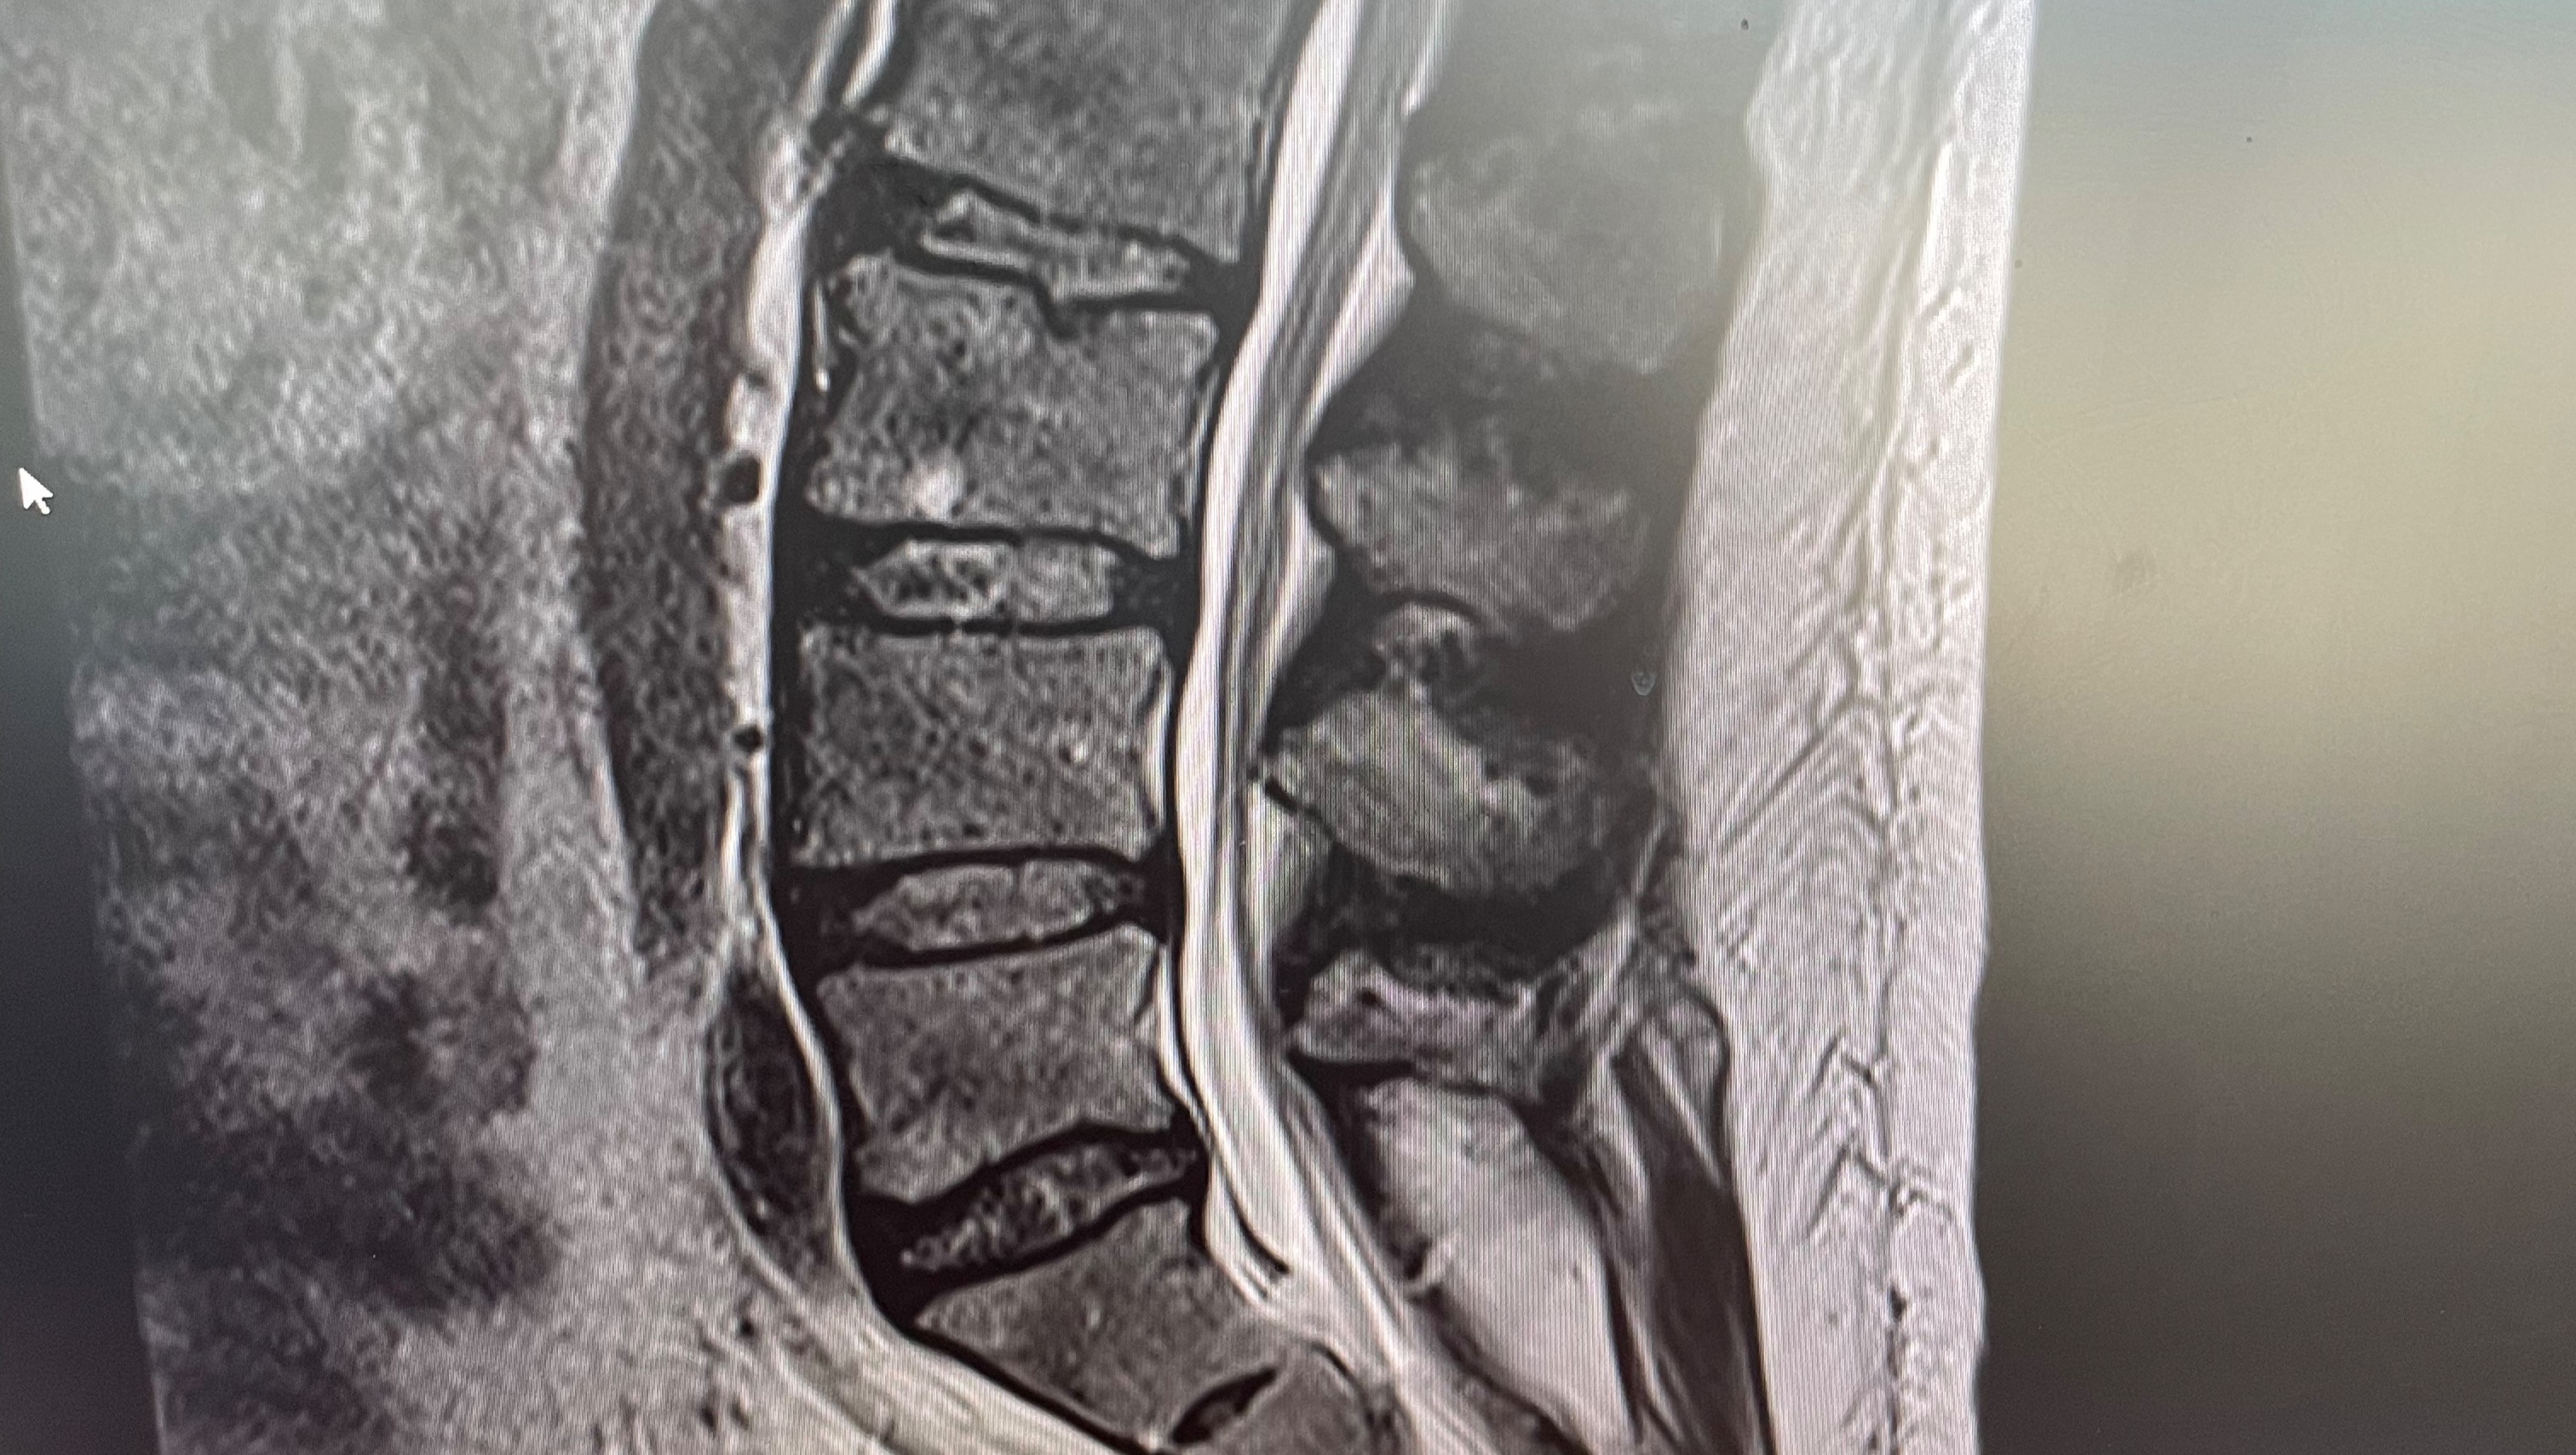

It has been almost two years this April since I was last in Charleston for neck surgery. Since then, I have worked to rehabilitate my neck and get my life back together. Sadly, this disease is vindictive and continues to impact my life. Living with Ehlers-Danlos Syndrome (EDS), a progressive connective tissue disorder has taught me that having a good care team is essential and not optional. For this to be possible, I have to travel. For this surgery, the condition being treated is Tethered Cord Syndrome. I was In a nutshell, this condition causes my spinal cord to be tethered to the wall of my spinal canal. As a kindergartener, little did I know that when I sat cross-legged and my legs fell asleep, tethered cord syndrome was the reason why. Typically, your spinal cord is supposed to hang freely at T11-12. My spinal cord is tethered to the wall of my spinal canal at L2.

Tethered cord syndrome has affected my ability to walk, my balance and coordination, bowel, and bladder function. Neurologically, this condition caused spasticity to surface in 2016 following my first neck surgery; it has been an ongoing problem since. I've had neuropathy throughout my lower body, and horrendously debilitating pain from the lumbar and sacrum to my toes.

The only treatment option for tethered cord syndrome is surgery. Unfortunately, surgery is not a cure. The surgery involves releasing (or detaching) the spinal cord from the wall of the spinal canal. This Summer, I am tentatively planning on traveling to Charleston to have my tethered cord released. While the operation is relatively short, the recovery is not. I'll stay at University Hospital in Charleston for at least three days and will need to stay in Charleston for another seven to eleven days. As you can imagine, the cost of lodging and food alone is going to be substantial. One major reason for the extended stay is cerebral spinal fluid (CSF) leaks. The surgery involves cutting away the tissue holding the spinal cord to the wall of the spinal canal. When you consider EDS weakens blood cells, tendons, ligaments, bone, etc. all of which are connective tissue, the risk for spinal fluid leaks is extremely high. If I were to have a CSF leak, my surgeon would have to open up my spinal column and invasively seal the leak.